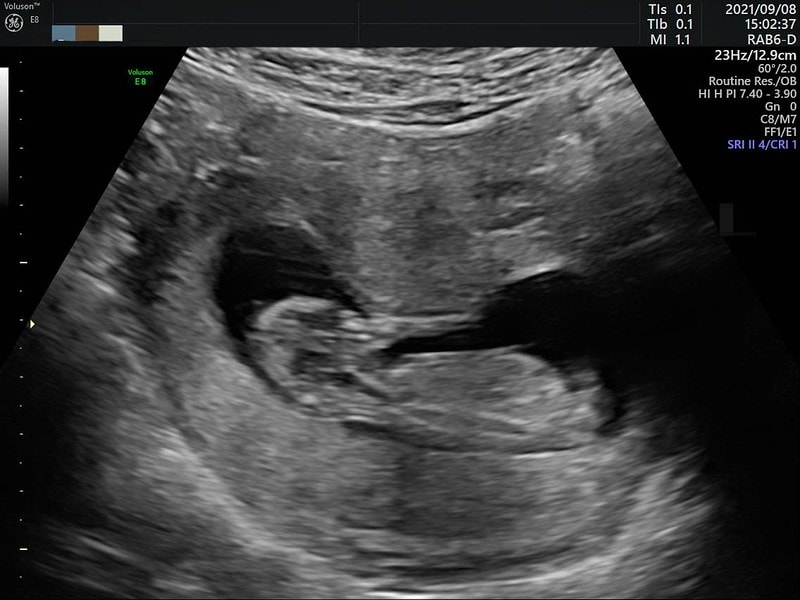

關於第一次聽到小孩的心跳

其實內心也是滿激動的

關於性別

很多人都很好奇的

我到20周都還沒公佈

其實16周產檢的時候就知道了

是個活潑的小男生唷!

看超音波好像沒有反轉的機會